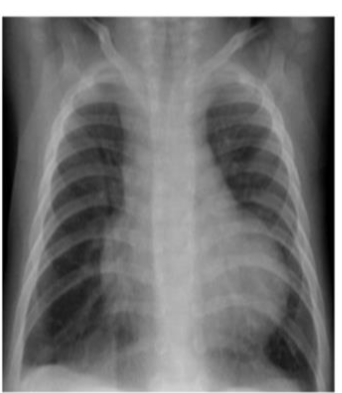

X-Ray Description:

- Cardiomegaly

- Enlargement of the right atrium and right ventricle is most apparent.

- Prominent pulmonary vascular markings.

- Differential Diagnosis (DDX): AVSD, ASD, VSD